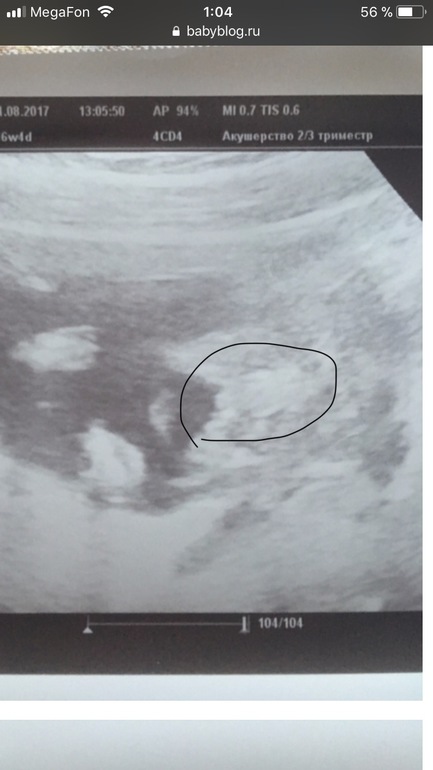

УЗИ, КТГ, доплерНа узи в 15,3 недели предположили мальчика) На 80%. Как вы думаете? На фото "вид снизу". Между ножек виднеется треугольничек) Без вариантов же, да? Пы.сы. рады любому полу, на узи ходили по другому вопросу, смотреть сердечко. Но хотелось бы точно знать))) А то мы имя уже придумали)

Вот по этому фото вообще не понятно кто. Я бы даже сказала что больше на девочку похоже или на кусочек пуповины.

Мне в 14 недель показали что то типо этого сказав что 70% мальчик. ( фото не мое а девочки с форума. ) у неё в итоге девочка родилась ! Хотя по фото очень похоже на мальчика ! Если не задумываться что на этом сроке у мальчиков нет яичек и половой бугорок есть у все) Спрашивала у другого врача она сказала что такой вид может быть у врех до 16 недель. Типо мальчики и девочки в таком сроке отличаются бугорком и вот круг или треугольник. Но я не видела такого ни у кого. Так что до 20 эта загадка так и остаётся ))

У нас тоже похожее на фото было изображение. Но сфоткать так не смогли потом - ребёнок убегал. Вот получился треугольничек)

Будем ждать) Врачу самой интересно стало, кто же) Крутила-вертела, вагинально посмотрела.